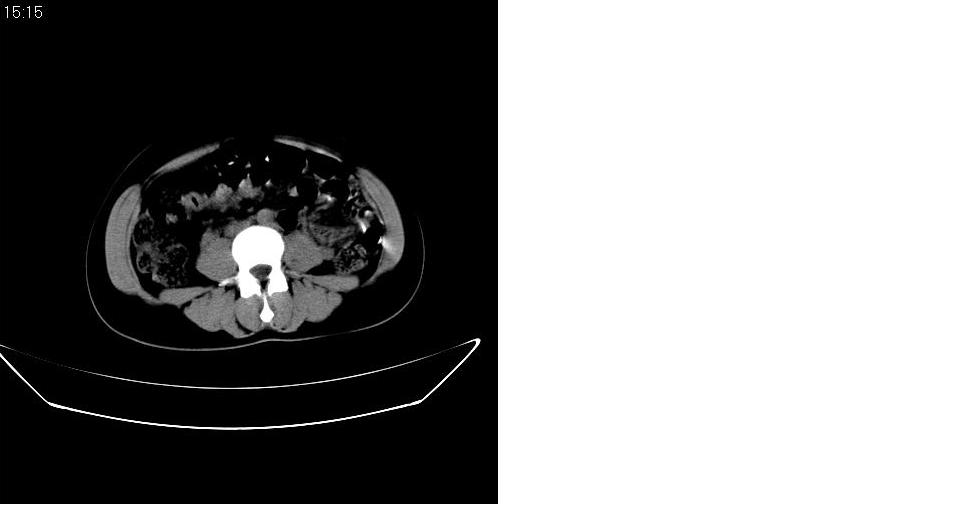

以下是引用求知若渴在2007-9-10 20:08:00的发言:[br]病变以脂肪成分为主,应该是错构瘤。另肝内胆管结石

以下是引用xulianj在2007-9-10 20:51:00的发言:[br]错构瘤,支持。含脂肪成分较多,证明较为成熟。

以下是引用王仕学在2007-9-10 21:34:00的发言:[br]有脂肪密度,哪怕是一点点,首先考虑错构瘤。还是增强吧,好说些!